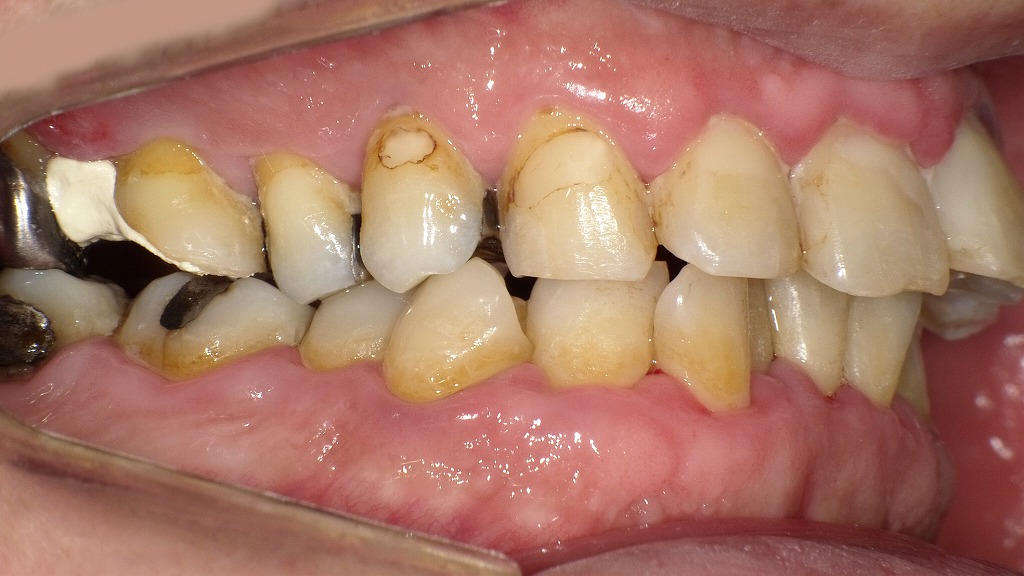

歯磨き不足によるプラーク残存による中等度歯周病の口腔内

歯磨きが不十分な状態では、歯面や歯間部にプラーク(歯垢)が多く残り、歯肉の炎症や出血、歯周ポケットの形成につながります。写真では、上下前歯部を中心に着色・歯垢の付着が認められ、歯肉の軽度腫脹も見られるなど、歯周病リスクが高い口腔内所見を示しています。適切なブラッシング指導と定期的なクリーニングが重要です。

この画像は、右側を中心に撮影された口腔内写真です。歯の表面や歯と歯ぐきの境目に、汚れや沈着物が多く見られます。以下のように分類して解説します。

🔹1. ステイン(着色)

矢印で示されている「ステイン」は、コーヒー・紅茶・タバコのヤニなどによる表面の着色汚れです。

歯の表面に付着しているだけなので、**歯科医院でのクリーニング(PMTCやエアフロー)**で比較的簡単に除去できます。

🔹2. 歯垢(プラーク)

中央部の「歯垢」は、**細菌のかたまり(バイオフィルム)**で、白っぽいまたは黄白色をしています。

歯ブラシが届きにくい歯と歯ぐきの境目に溜まりやすく、放置すると歯石に変化します。

歯垢が残ると、歯肉炎や歯周病の原因になります。

🔹3. 歯石

右側に示されている「歯石」は、歯垢が唾液中のカルシウムと結合して石灰化した硬い沈着物です。

表面がザラついており、さらに新しい歯垢が付きやすくなるため、歯周病を悪化させる原因になります。

自分では除去できないため、**歯科医院でのスケーリング(歯石取り)**が必要です。

🔹4. タバコのヤニの影響

歯の全体に茶褐色のヤニの沈着が見られます。

ヤニは歯垢や歯石の付着を助長し、歯ぐきの血流を悪化させるため、歯周病を進行させやすい要因です。

🔹5. 歯周病の進行状況

歯ぐきがやや下がり、歯と歯の間が広がって見えます。

また、歯石の沈着量や歯ぐきの炎症の程度から判断すると、**中等度の歯周病(歯周炎)**が疑われます。

歯を支える骨が部分的に吸収している可能性もあります。

🔹まとめ

この状態は、

- 歯石・歯垢の除去(スケーリング)

- 着色除去(エアフロー)

- 禁煙やブラッシング指導

を行うことで改善可能です。

ただし、すでに歯周病が進行している場合は、歯周外科などの歯周治療が必要になります。